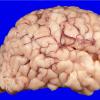

Menkes disease (4)